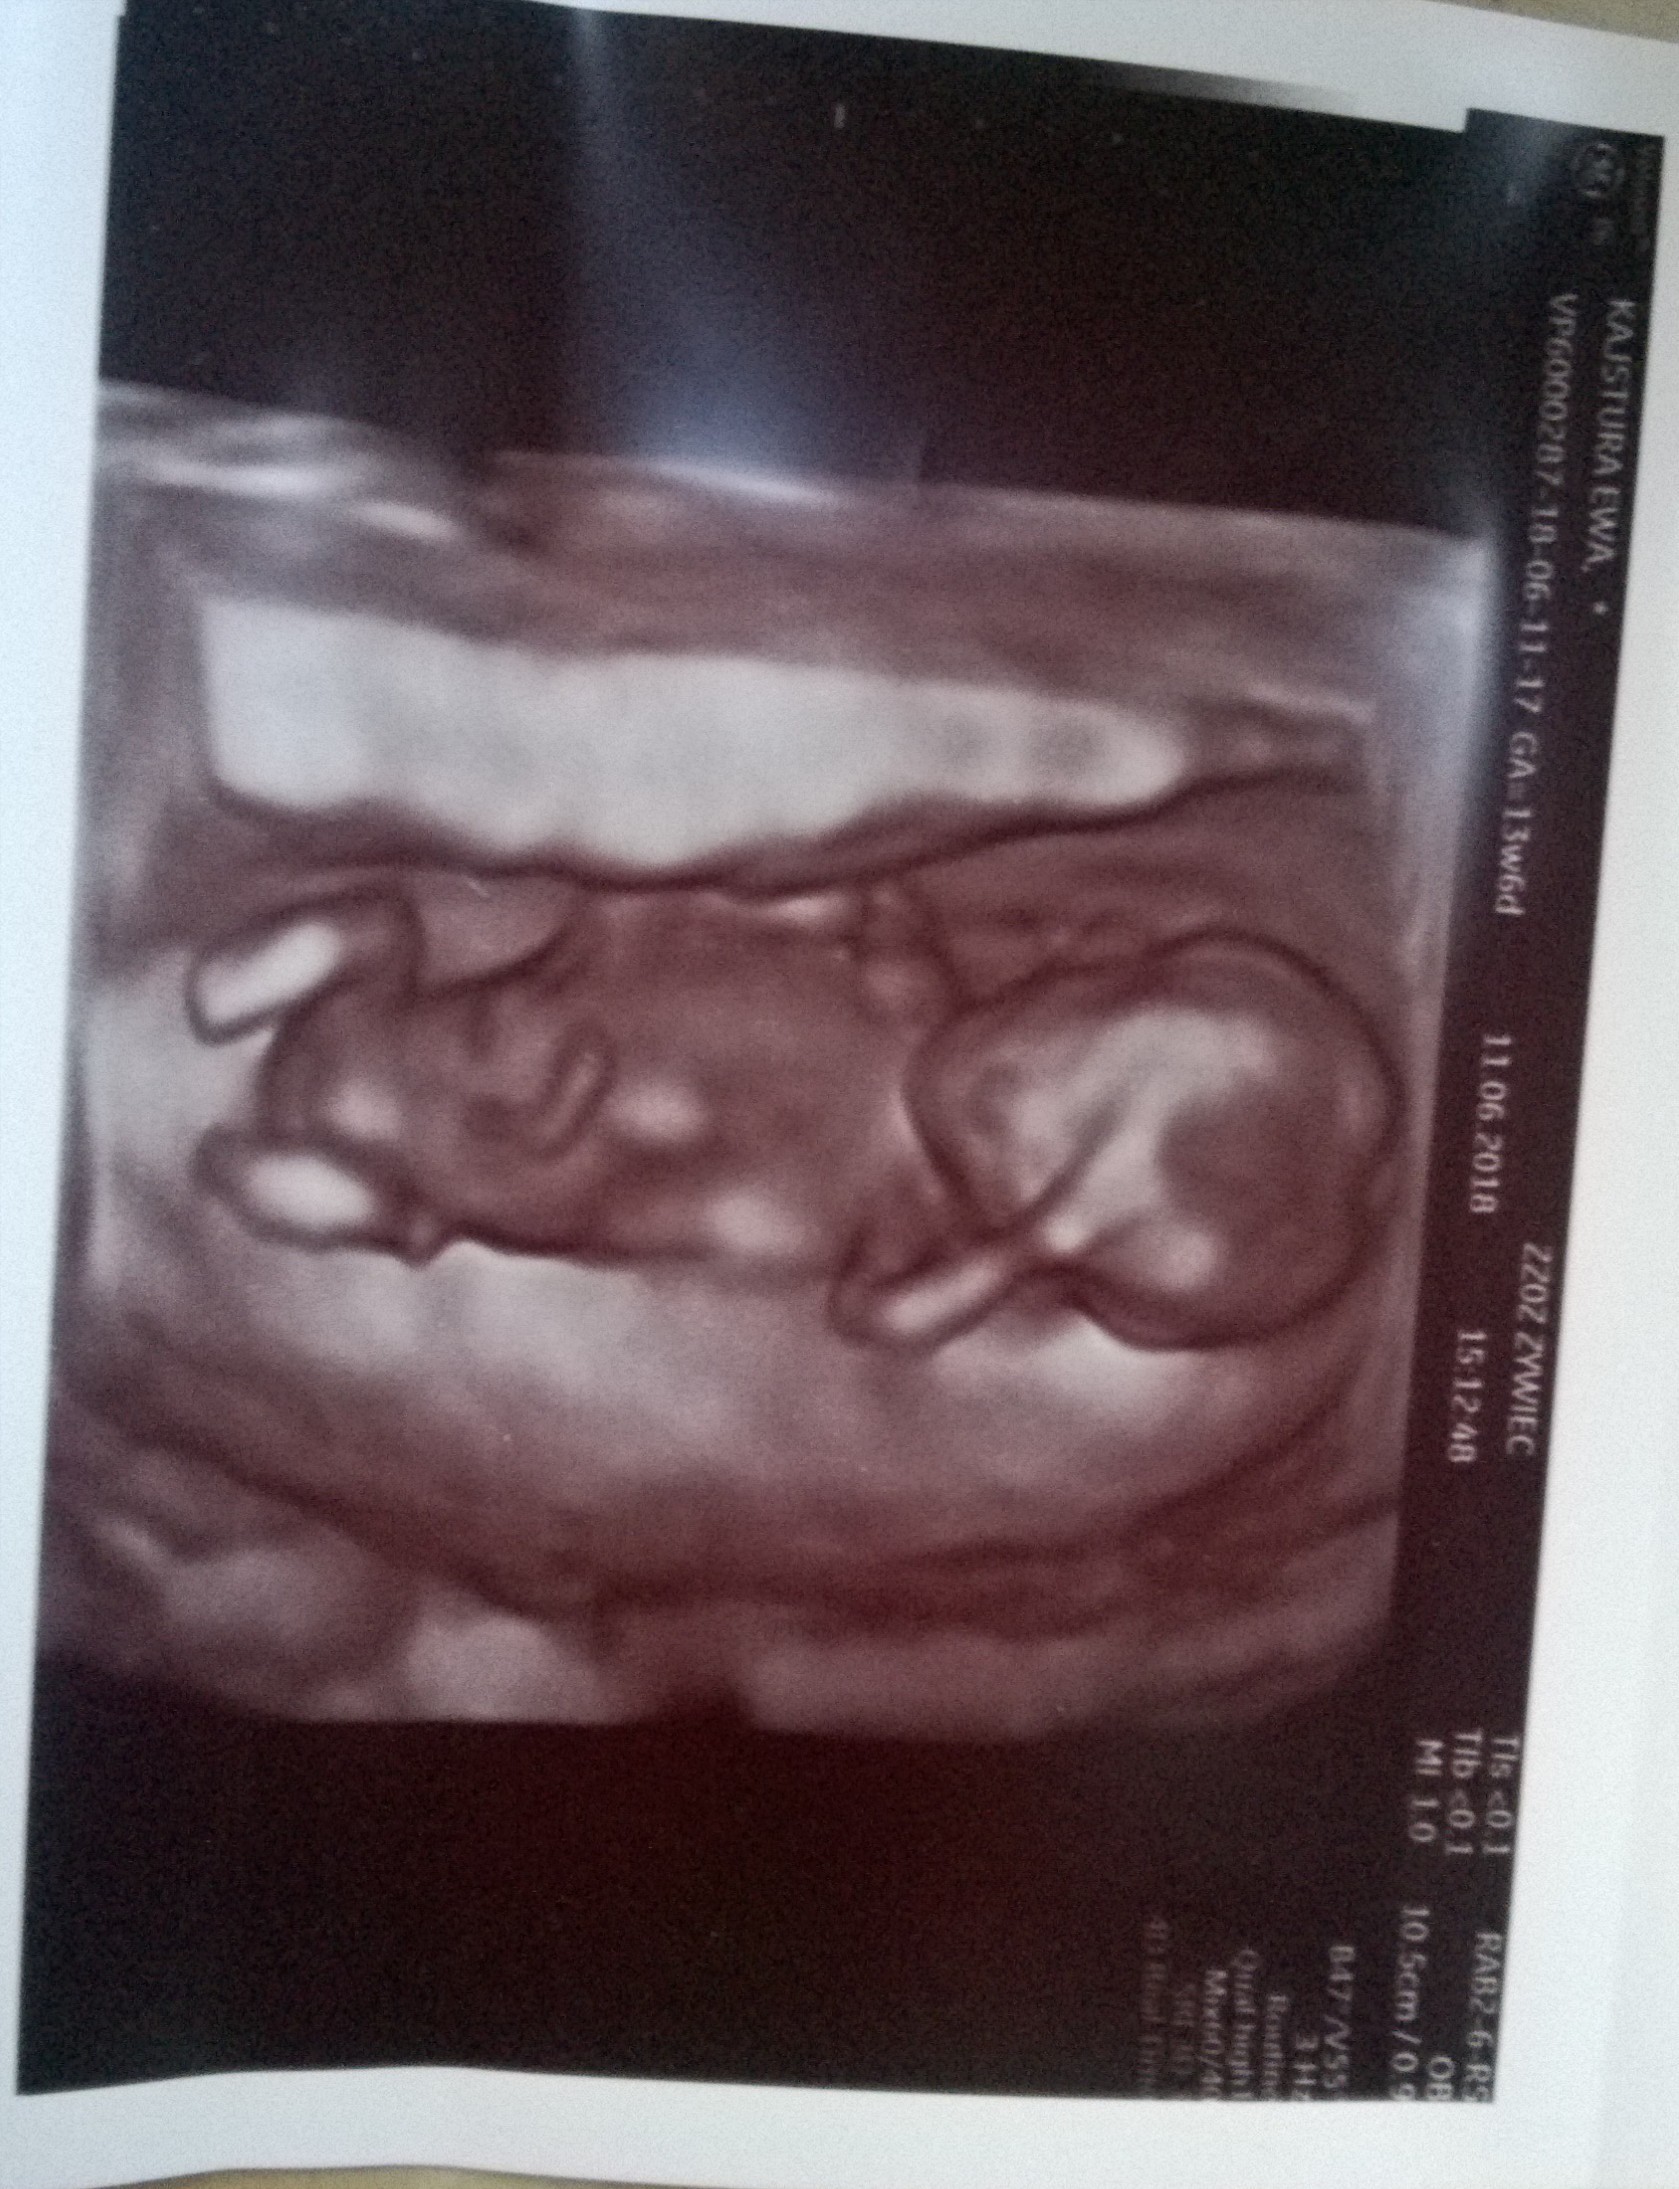

Serduszko pieknie mi bije..

Mama twierdzi, że będe jednak Remek

No i tyle sie dowiedzialam. Dostalam skierowanie na krew bo okazalo sie ze nie ma wszystkiego ☺

Kolejna wizyta 16 lipca ☺

Zobacz załącznik 866827